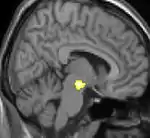

La morphométrie voxel par voxel (VBM) montre les différences structurelles des zones du cerveau

Les images par tomographie à émission de positron indiquent les régions du cerveau qui sont activées lors de la douleur, par rapport aux périodes sans douleur. Elles montrent les régions du cerveau qui sont toujours actives durant la douleur en jaune/orange (appelé "matrice-douleur"). La zone au centre (dans les trois vues) est spécifiquement activée uniquement pendant la crise. Les photos sur la ligne du bas (effectuées par VBM) montrent les différences structurelles entre les patients souffrant d'AVF et des personnes saines : seulement une partie de l'hypothalamus est différente[50],[51].